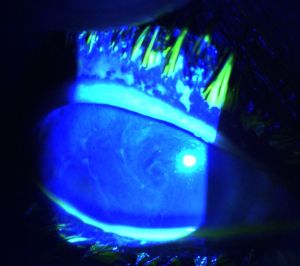

Hurricane keratopathy, or hurricane keratitis, was first described after penetrating keratoplasties by Mackman et al.[1] It is characterized by a whorled pattern seen in the epithelial layer that is highlighted by fluorescein. It appears to be due to increased corneal epithelial turnover, which is also seen in rigid contact lens wearers and with long-term steroid use [2][3]

The whorled pattern stains with fluorescein, distinguishing it from similar-appearing cornea verticillata. The term “vortex keratopathy,” another name for cornea verticillata, has also been used to describe hurricane keratopathy.[4][5] However, some authors reserve the terms “vortex keratopathy” and “cornea verticillata” to describe non-staining patterns and hurricane keratopathy to describe those that stain.[3][6] When the pattern appears more random but has the same pathoetiology as hurricane keratopathy, the term blizzard keratopathy has been used.[2]

Clinical Diagnosis

The hallmark of hurricane keratopathy is the presence of a whorl-like pattern of epithelial cells that appear as whorled white or grayish-brown lines on the cornea. The pattern is clockwise in the majority of patients. Hurricane keratopathy can be differentiated from vortex keratopathy due to the positive fluorescein stain, which is not observed with the latter.[3][7]